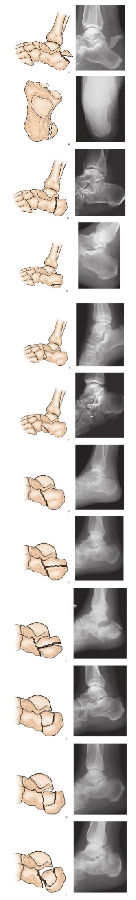

2、Essex-Lopresti分型:

Essex-Lopresti分型基于侧位X线片,根据骨折是否累及距下关节面分为两型:Ⅰ型未累及距下关节;Ⅱ类累及距下关节。根据Ⅱ型骨折继发骨折线的走行,又将其分为舌形骨折和关节面塌陷形骨折。这种分类方法简单易用,但关节面塌陷性骨折太过笼统,不利于不同骨折类型的评价和临床预后(图14)。

图14 Essex-Lopresti分型

A. Ⅰ型:骨折未累及距下关节A跟骨结节骨折:A1鸟嘴样骨折

B. Ⅰ型:骨折未累及距下关节,A2内缘撕脱骨折

C. Ⅰ型:骨折未累及距下关节,A3垂直骨折

D. Ⅰ型:骨折未累及距下关节,A4水平骨折

E. Ⅰ型:骨折未累及距下关节,B累及跟骰关节,B1鹦鹉鼻型

F. Ⅰ型:骨折未累及距下关节,B2其他类型

G. Ⅱ型:骨折累及距下关节,A舌形骨折,A1继发性骨折线水平向后行至跟腱止点的远侧,舌形骨片包括跟骨体上面和后关节面的外侧部

H. Ⅱ型:骨折累及距下关节,A2继发性骨折线水平向后行至跟腱止点的远侧,舌形骨片包括跟骨体上面和后关节面的外侧部。舌形骨折,继发性骨折线走向跟骨结节后缘,移位不明显

I. Ⅱ型:骨折累及距下关节,A3继发性骨折线水平向后行至跟腱止点的远侧,舌形骨片包括跟骨体上面和后关节面的外侧部。舌形骨折,骨片前端陷入跟骨体松质骨内,后端上翘,骨折块分离移位

J. Ⅱ型:骨折累及距下关节,B关节面塌陷骨折,B1继发性骨折线经跟骨体部行至后关节面与跟腱的附着点之间。塌陷形骨折,继发性骨折线经过体部走向关节后面,无明显移位

K. B2继发性骨折线经跟骨体部行至后关节面与跟腱的附着点之间。塌陷形骨折,关节面骨片移位,陷入跟骨体松质骨内

L. B3继发性骨折线经跟骨体部行至后关节面与跟腱的附着点之间。塌陷形骨折,原始骨折线处分离